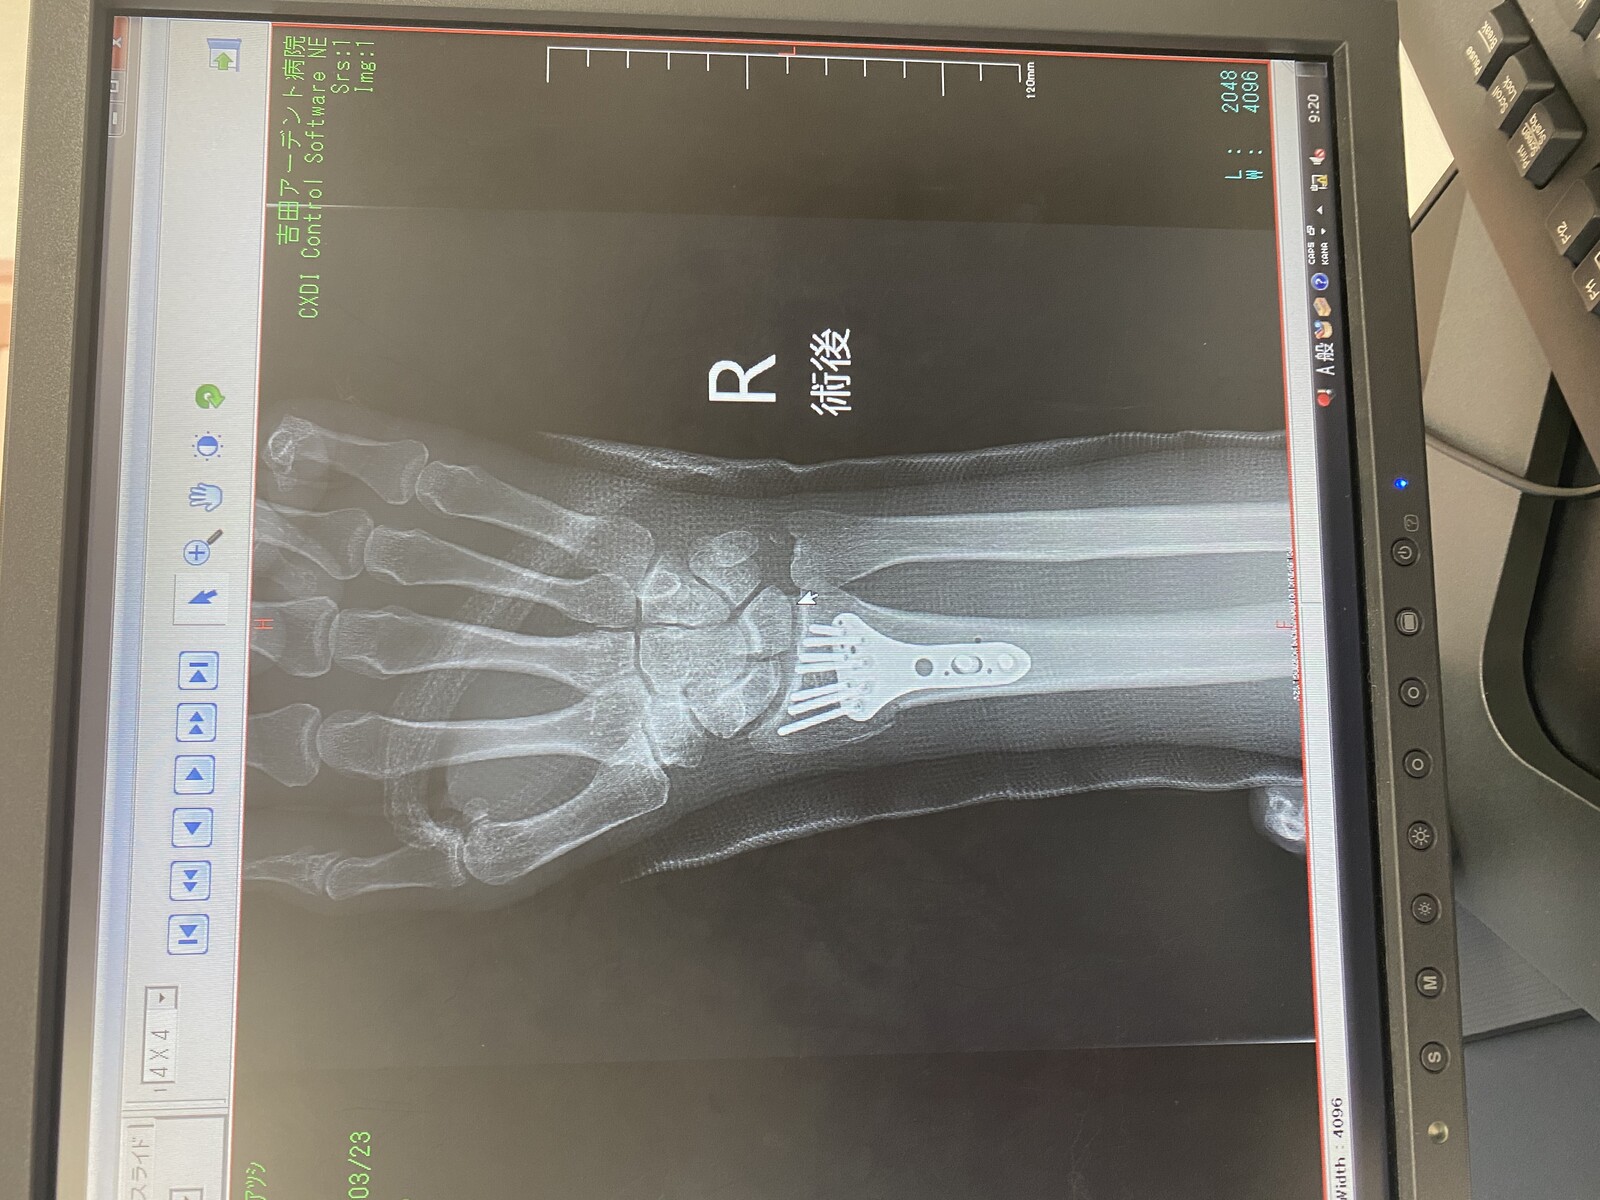

最後におかんの採血なんやけど、右腕はギブスであかんし